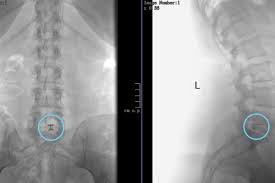

Prof Dr Christian Woiciechowsky Neurochirurgie Berlin Wirbelgleiten